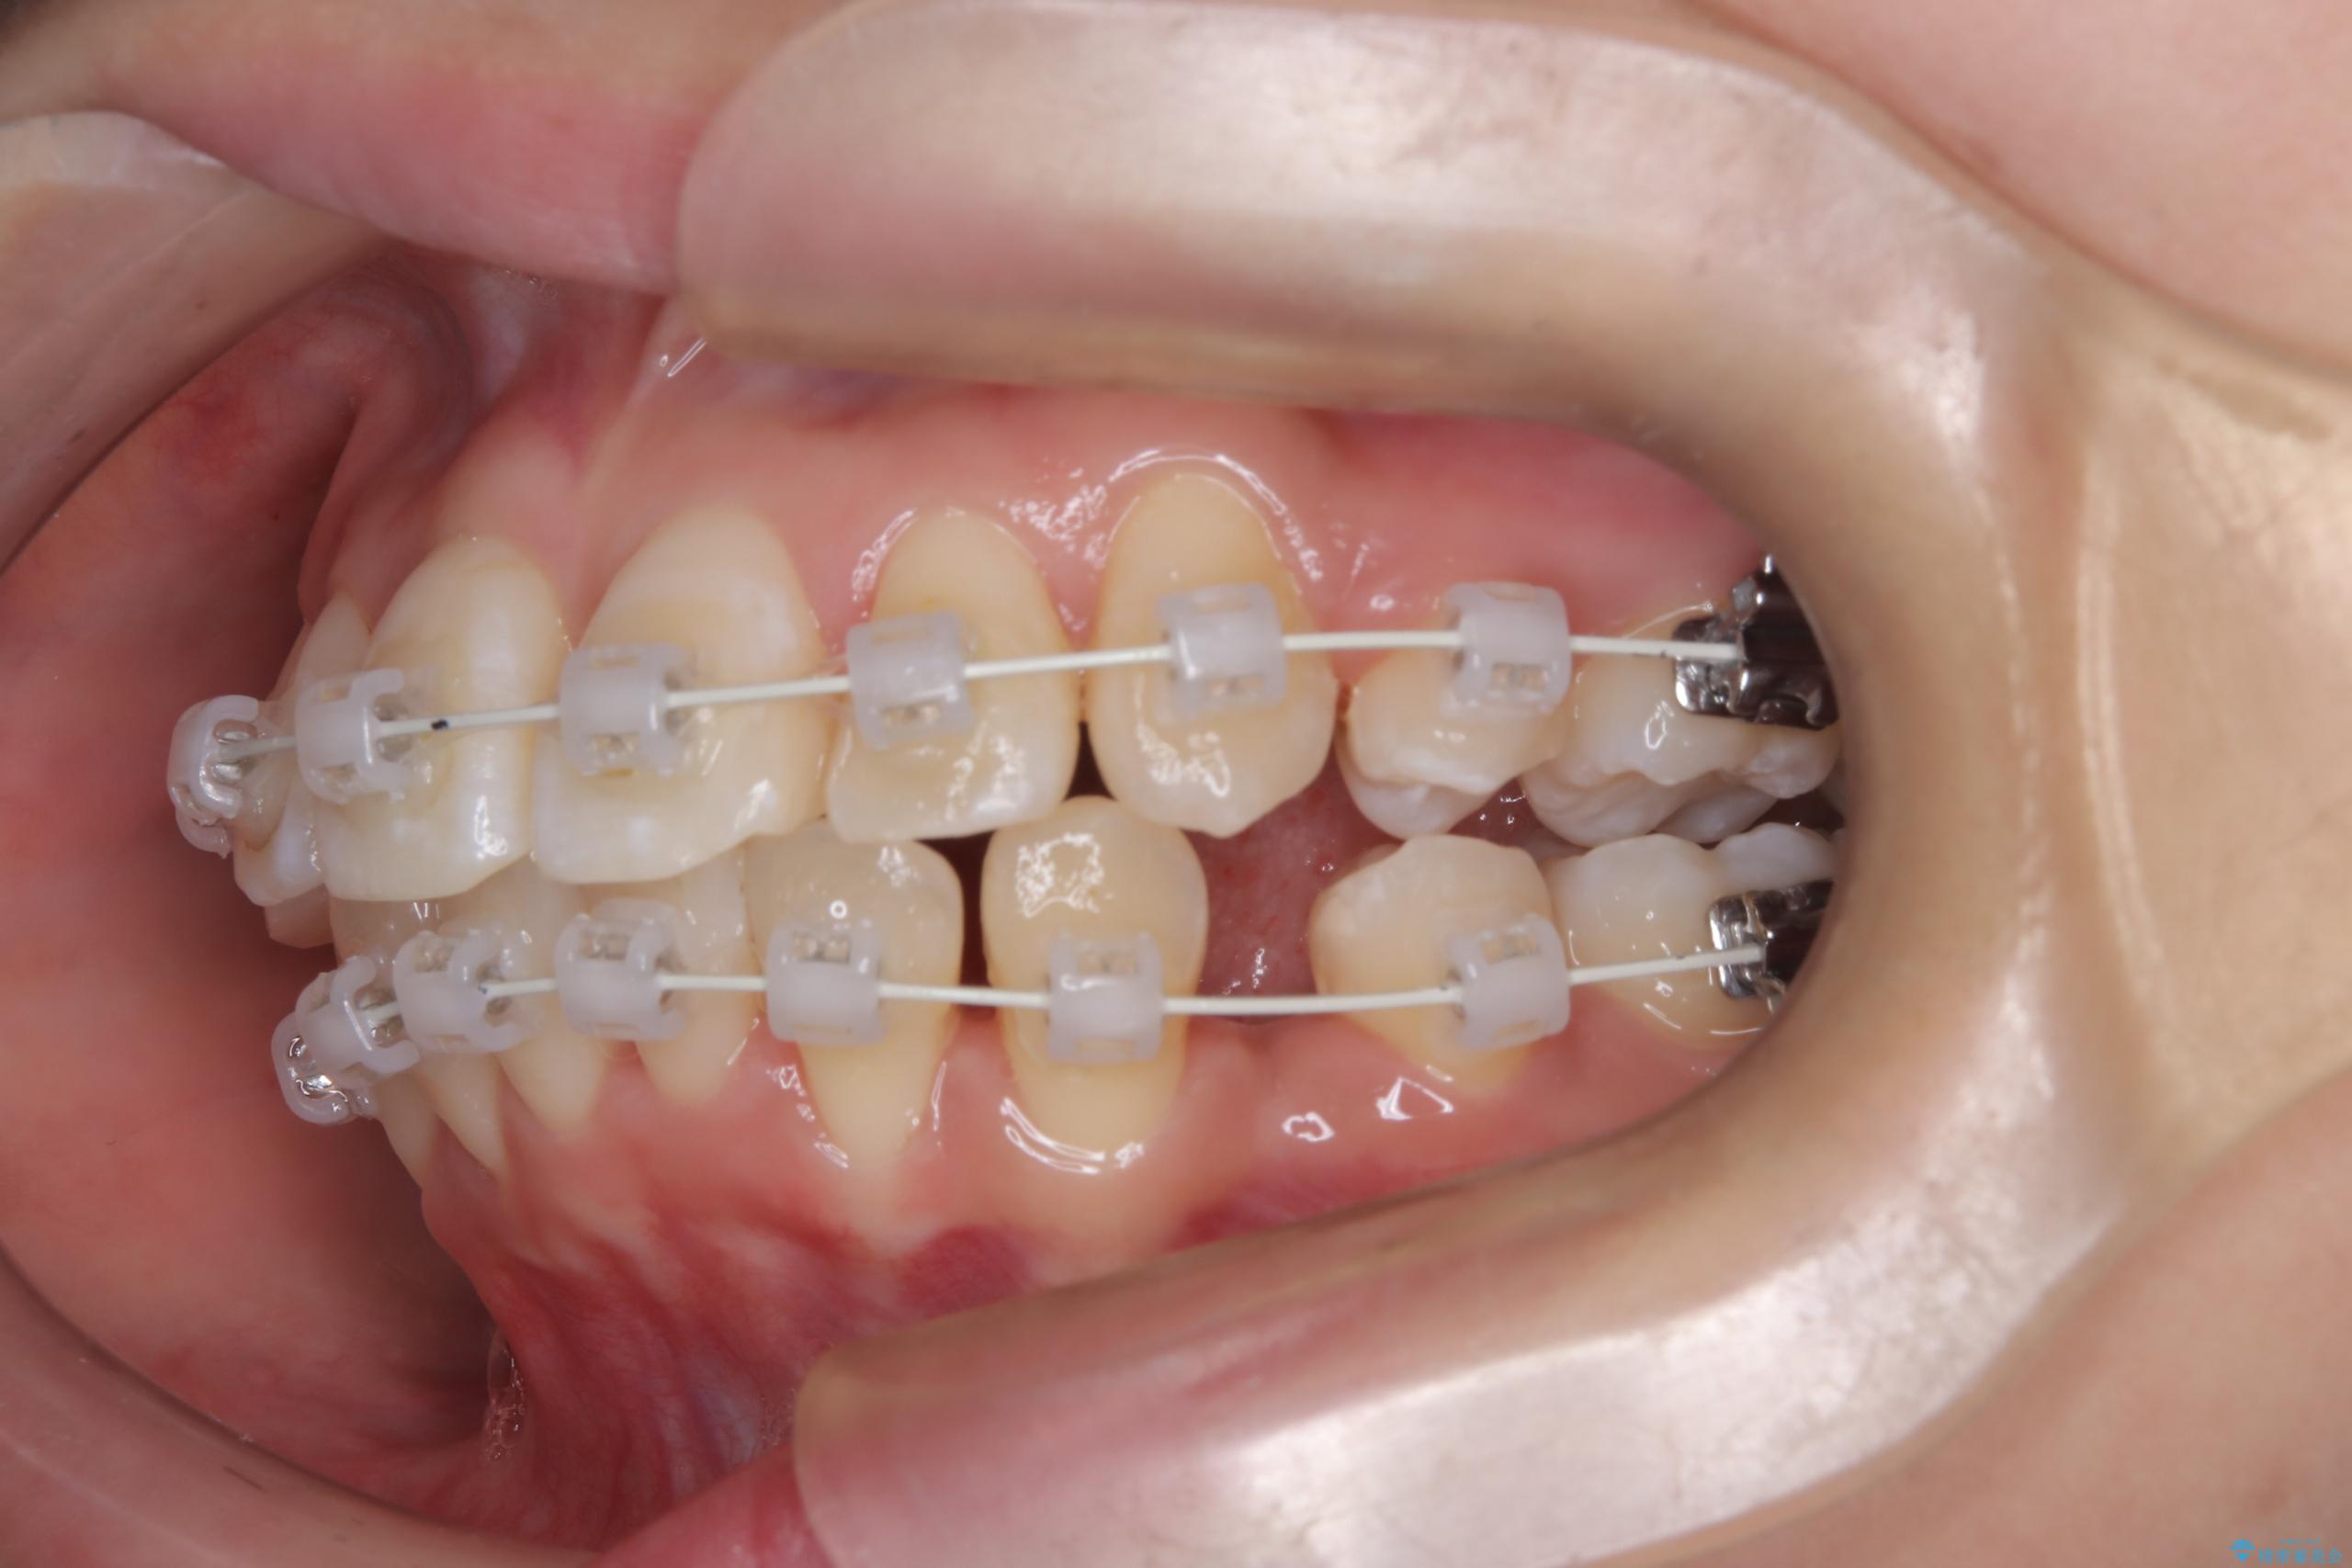

今回の矯正治療では、まず計画通り上下左右の小臼歯4本を抜歯し、八重歯や正中のズレを解消するための十分なスペースを確保しました。装置には、目立ちにくい白いブラケットとワイヤーを使用した審美ワイヤー矯正を採用。

八重歯: 突出していた八重歯を歯列内に誘導し、デコボコを解消しました。

正中のズレ: 歯を左右対称に移動させることで、上下の歯の中心線を正確に合わせ、顔全体のバランスも改善しました。

治療の結果、長年気にされていた八重歯と正中のズレが解消し、機能的にも整った理想的な歯並びを獲得。目立たない装置で治療を完遂し、自信を持って笑える美しい笑顔を手に入れていただけました。